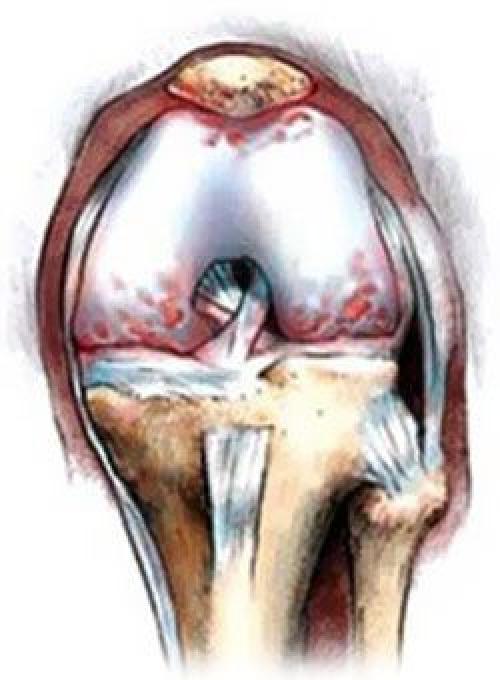

При артрозе истончается хрящевая соединительная ткань сустава, тем самым травмируя кости

Истончение гиалинового хряща коленного сустава. Характер возникающей проблемы

Хрящ в коленной области – одна из самых сложных структур в организме человека, выполняющих ежедневное функциональное назначение, без которого невозможно представить себе нормальную жизнедеятельность и двигательную активность. Тонкий хрящ, покрывающий и предохраняющий поверхности костей, образующих коленный сустав, эластичен и призван сглаживать движения человека, исключая возможность межкостевого трения. Как и все остальные тонкие хрящи в суставах, он амортизирует испытываемые нагрузки.

Хрящ колена у некоторых людей начинает разрушаться еще до наступления 30 лет, и происходит это по разным объективным причинам. К 45 годам уже наступает полноценно развивающийся процесс разрушения хрящевой ткани, выражающийся в ее изначальном повреждении и возникновении микротрещин, затем в появлении обширного воспалительного процесса, за которым следует разрастание и деформация костной ткани. Заболевание, у которого есть общий собирательный термин артрит, развивается по нескольким причинам.